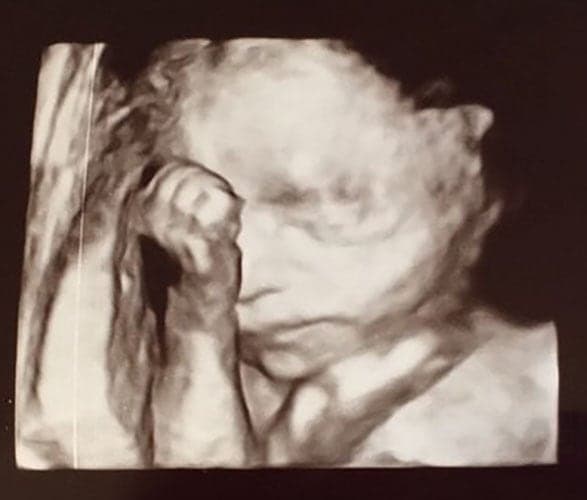

Ultraschallbilder aus dem 3. Trimester (29. bis 40. SSW)

Im dritten Trimester der Schwangerschaft ist das Baby so groß, dass es nicht mehr komplett auf ein Ultraschallbild passt. Nun kann man wunderbare 3D-Ultraschalle des Gesichts machen. In diesem Semester nehmen die Babys nochmal rasant zu und wer Glück hat, kann auf seinem Ultraschall schon erste Gesichtszüge erkennen.

Was genau man auf einem Ultraschallbild erkennen kann, hängt nicht nur von der Größe des Babys ab, sondern auch davon wie gut das Ultraschall-Gerät ist, mit dem die Aufnahme gemacht wurde. Auch auf den Ultraschallbildern hier kannst du sehen, dass die Qualität stark schwankt. In der Regel kann man gut den Kopf und RUmpf des Babys erkennen und auch die Gliedmaßen erkennt man selbst als Laie gut.

Wer sich jedoch erhofft Gesichtszüge zu erkennen, der wird oft enttäuscht. Zwar kann man beim 3D-Ultraschall schon eine Menge sehen, aber das umgebende Fruchtwasser sorgt in den allermeisten Fällen für starke Störungen.